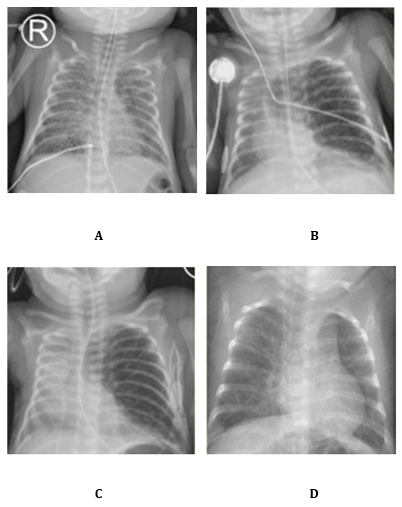

Due to severe nRDS, three doses of surfactant were administered. The first was given at 3 hours of life using less invasive surfactant administration (LISA). At 4 hours, he was intubated and placed on high-frequency oscillation (HFO) ventilation. Ventilation settings included mean airway pressure (MAP) of 8-10 cmH?O and a maximal amplitude of 28. Permissive hypercapnia was accepted with PaCO? up to 65 mmHg. Despite these measures, the respiratory condition deteriorated. Chest radiography revealed severe bilateral PIE (Image 1A). Conservative management was started, consisting of strict lateral positioning and strict lung-protective ventilation strategies. The main challenge was to maintain adequate MAP for gas exchange while avoiding further overdistension.

Clinical deterioration

At one week of life, the infant was extubated to non-invasive neurally adjusted ventilatory assist (NIV-NAVA) with PEEP 8 and level 1 support. Within 24 hours, pulmonary emphysema worsened. Chest X-ray showed marked left lung overexpansion with mediastinal shift to the right (Image 1B). He was re-intubated to prevent further overdistension. Ventilation was continued with HFO alternated with a short period of NAVA. MAP was maintained at 8-10 cmH?O.

Because of severe PIE with left lung overexpansion, with selective intubation considered unsafe, high-dose intravenous corticosteroids were initiated by team consensus. On day of life (DOL) 11 treatment started at 0.3 mg/kg/day for three days. Therapy was then switched to the oral route with a gradual taper (Table 1). On DOL 14, the regimen was reduced to 0.2 mg/kg/day in two oral doses (0.13 mg each). The infant was successfully extubated on DOL 15 (Image 1C).

Further tapering followed: 0.15 mg/kg/day on DOL 16, 0.10 mg/kg/day on DOL 18, 0.05 mg/kg/day on DOL 21. However, due to progressive tachydyspnoea and oxygen dependency under CPAP (PEEP 6.5, FiO? 40–55%), the dose was temporarily increased to 0.15 mg/kg/day on DOL 22. The cumulative dose at that point was 1.8 mg/kg. From DOL 26 onward, gradual tapering resumed: 0.12 mg/kg/day, 0.10 mg/kg/day on DOL 27, 0.08 mg/kg/day on DOL 29 and 0.05 mg/kg/day on DOL 31. The final dose was administered on DOL 33 (Image 1C). The total cumulative dose over the 22-day course was 3.15 mg/kg. The rationale for this regimen was to reduce airway inflammation, improve gas exchange and facilitate extubation. The initial high dose was chosen to achieve a rapid effect, followed by a slow taper to allowing stable weaning on non-invasive support, avoiding rebound deterioration and preventing re-intubation.

Image 1.  A Bilateral PIE , B Unilateral PIE, left lung overdistension with mediastinal shift , C Unilateral PIE with diminution of overdistension D No signs of PIE or overdistension.